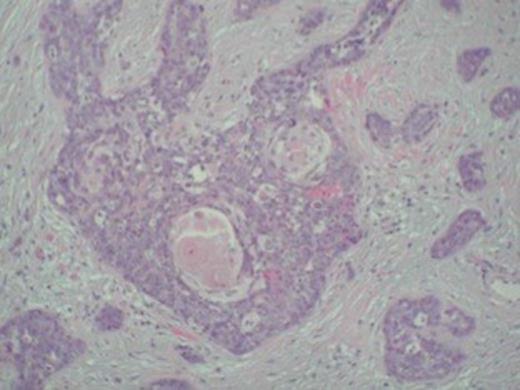

Keratin pearls confirming squamous cell carcinoma metastasis in the tumour specimen

Despite an initial response to treatment, four months later, the patient presented with clinical picture suggestive of large bowel obstruction. An explorative laparotomy unveiled a large mass involving the terminal ileum and caecum along with dense adhesions of ileocaecal loops. A 4 cm nodule in the right lobe of liver was also discovered. The patient underwent right hemicolectomy with an end-to-end ileocolic anastomosis. The surgical specimen consisted of 21 and 15 cm length of small and large bowel, respectively. The central 10 cm of the bowel was of undeterminable nature due to its tortuous nature caused by innumerable adhesions. The mucosa was unremarkable except for focal oedema. Histological examination showed poorly-differentiated squamous cell carcinoma infiltrating serosa with prominent intravascular spread. The tumour was predominantly confined to the peritoneal fat and serosa with no obvious invasion of the muscularis, submucosal, and mucosal layers (Figure 1 and 2). The appearance was consistent with metastatic spread from primary anal lesion. Unfortunately, the patient did not recover and died from multiple organ failure on the fourth post-operative day.